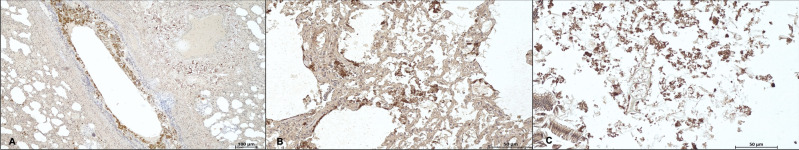

Sudden unexpected infant death (SUID) encompasses both explained and unexplained infant fatalities. When a comprehensive investigation yields inconclusive results, the case is classified as sudden infant death syndrome (SIDS). On the other hand, the most frequent non-SIDS diagnoses may be attributed to specific causes of death including a heterogeneous spectrum of conditions and disorders (e.g., trauma, asphyxia, suffocation, infection and metabolic diseases). Although rare, milk aspiration is a recognized cause of SUID that can lead to acute respiratory failure. This case report describes the death of a three-month-old infant found unresponsive in a traditional African baby carrier. Gross examination revealed no significant anomalies other than increased lung weight and the presence of milk-like material in the airways, alveoli, and stomach. Histological and ultrastructural analyses identified granular brownish material with birefringent globules in the lungs, consistent with aspirated milk. Immunohistochemical staining was positive for beta-lactoglobulin, confirming formula milk aspiration. This evidence was crucial in excluding maternal negligence as a cause of death, instead supporting an ante-mortem aspiration event resulting from regurgitation. This case highlights the diagnostic challenges associated with fatal milk aspiration and emphasizes the critical importance of a multidisciplinary approach. The integration of clinical history, autopsy findings, and advanced histopathological techniques is essential for accurately determining the cause of death and ensuring a sound legal assessment within the Courtroom setting.

婴儿意外猝死(SUID)包括可解释的和无法解释的婴儿死亡。当全面调查没有得出确定的结果时,该病例被归类为婴儿猝死综合征(SIDS)。另一方面,最常见的非小岛屿发展中国家诊断可归因于具体的死亡原因,包括各种各样的病症和失调(例如,创伤、窒息、窒息、感染和代谢疾病)。虽然罕见,吸乳是SUID的公认原因,可导致急性呼吸衰竭。本病例报告描述了一名三个月大的婴儿在传统的非洲婴儿背带中发现无反应死亡。大体检查除肺重量增加及气道、肺泡和胃内有乳样物质外,未见明显异常。组织学和超微结构分析发现肺部有褐色颗粒状物质,有双折射球,与吸乳一致。免疫组化染色-乳球蛋白阳性,证实误吸配方奶。这一证据对于排除产妇疏忽作为死亡原因,而不是支持由反流引起的死前误吸事件至关重要。本病例强调了与致命吸乳相关的诊断挑战,并强调了多学科方法的关键重要性。综合临床病史、尸检结果和先进的组织病理学技术对于准确确定死亡原因和确保在法庭环境下进行合理的法律评估至关重要。